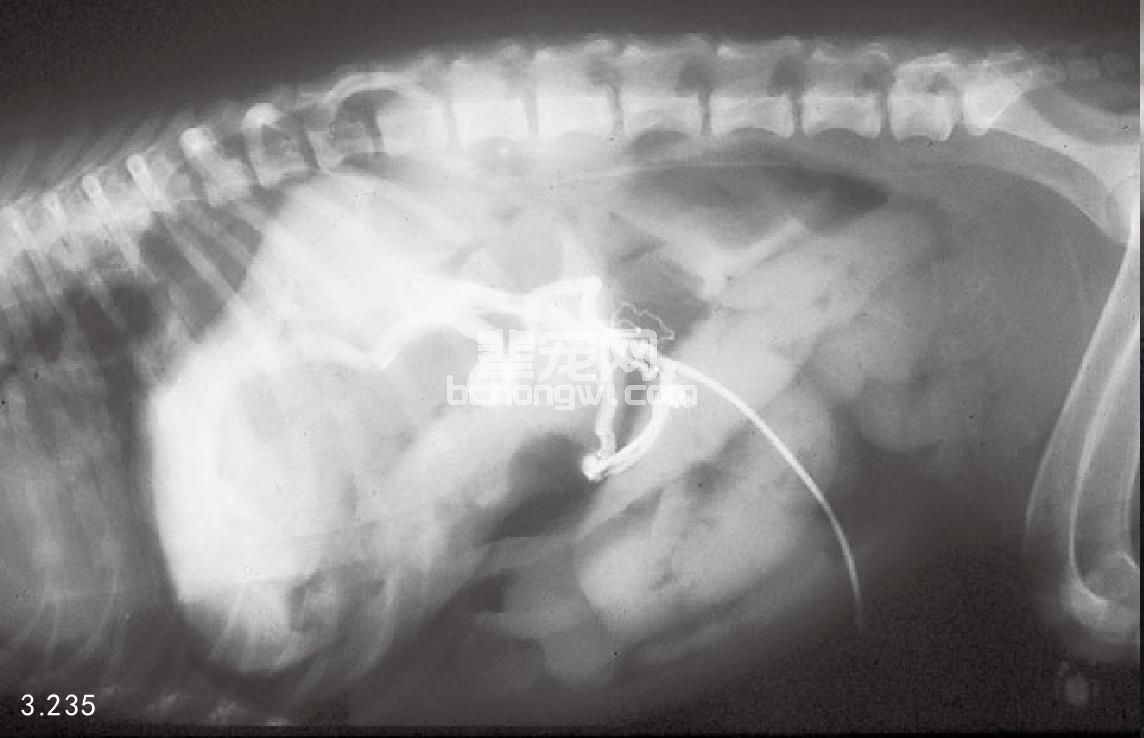

图3.235 2岁拉萨犬肠系膜静脉门静脉造影确诊的静脉分流。